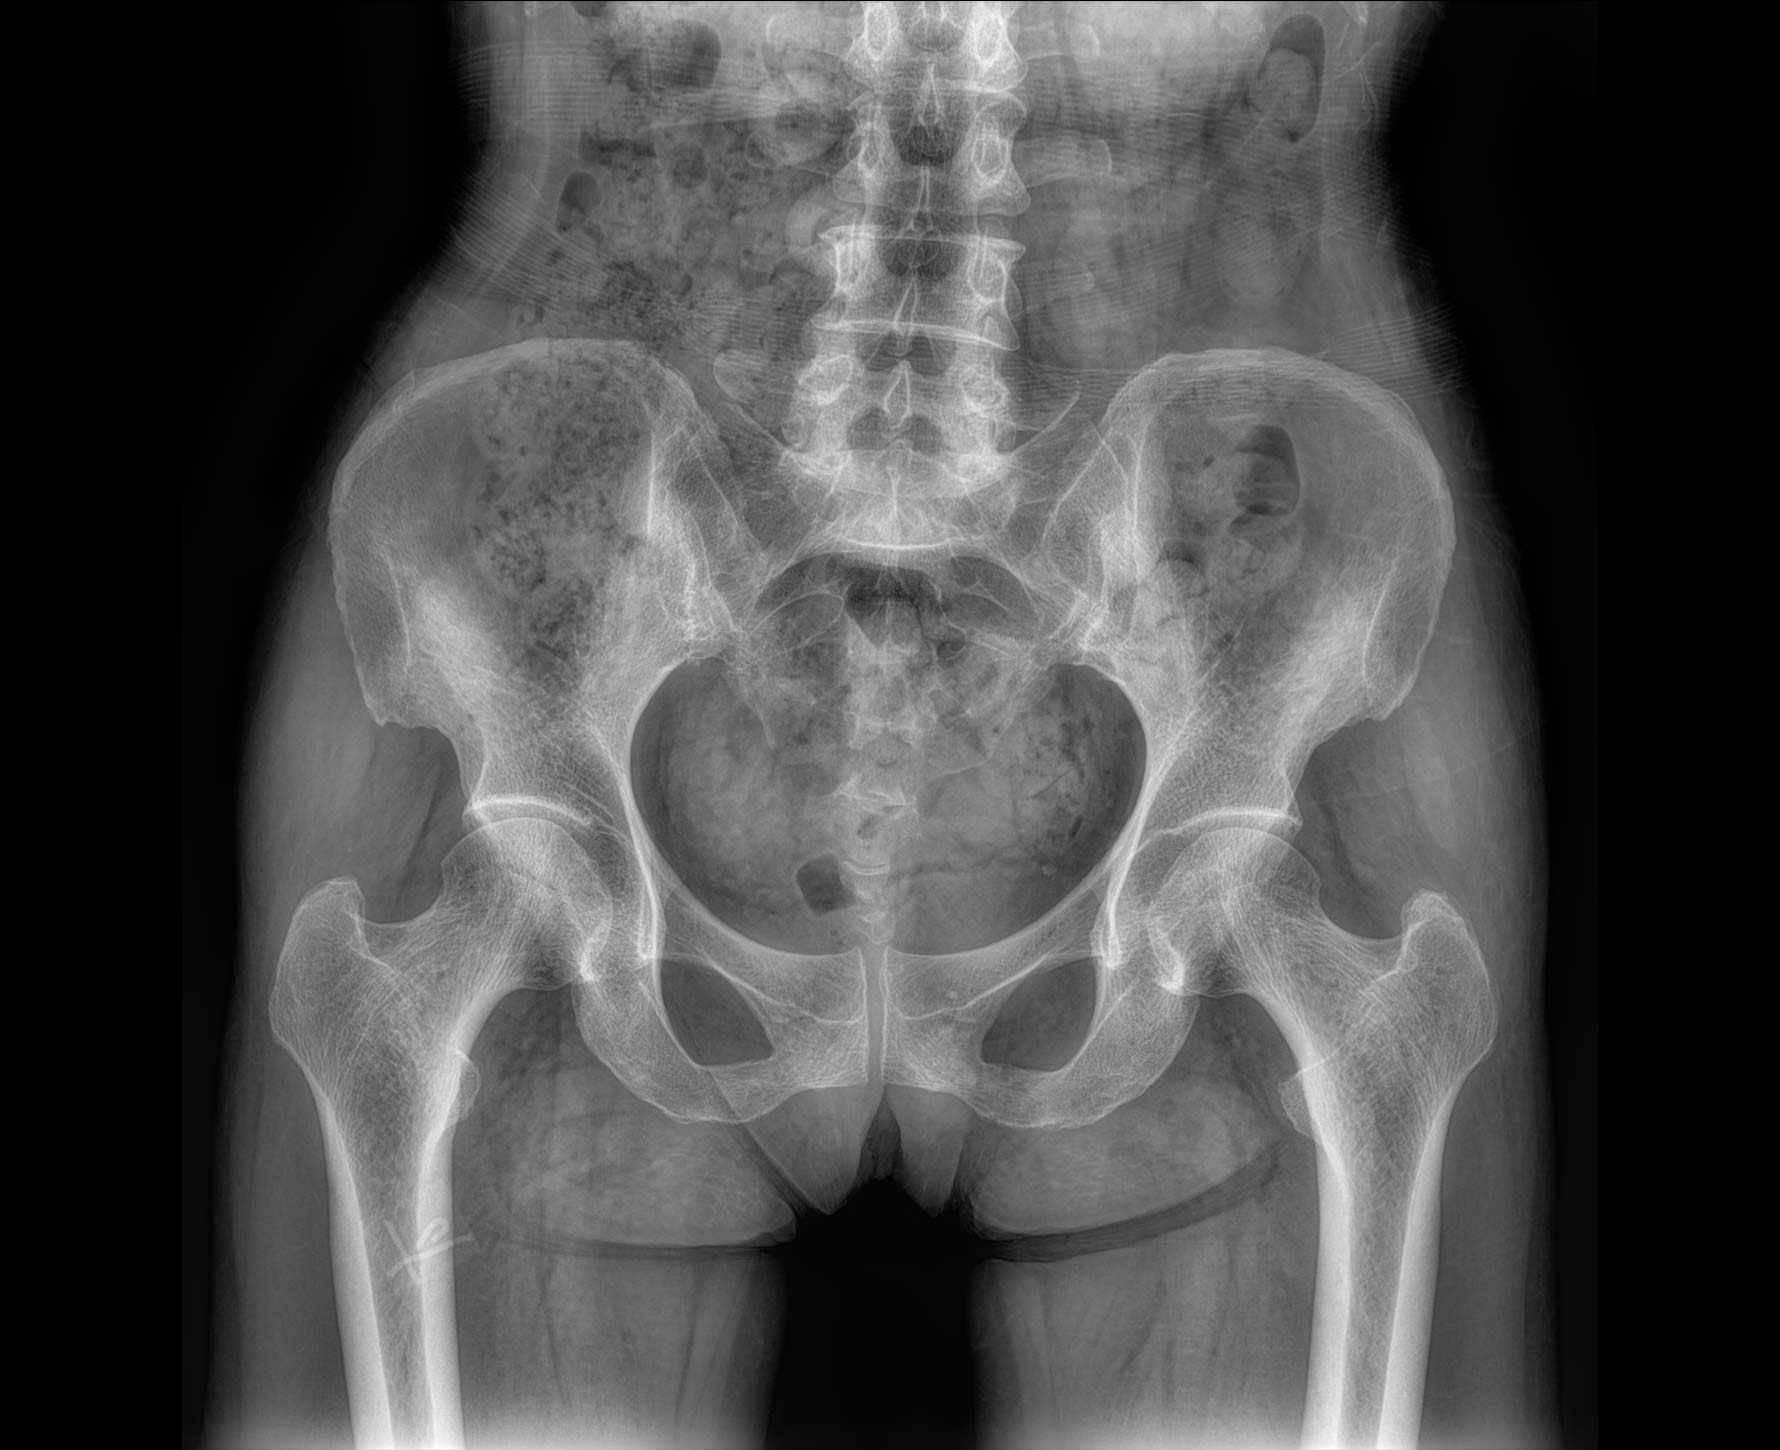

• 拍片

适用于全身各部位摄影

(常规摄影和特殊摄影)